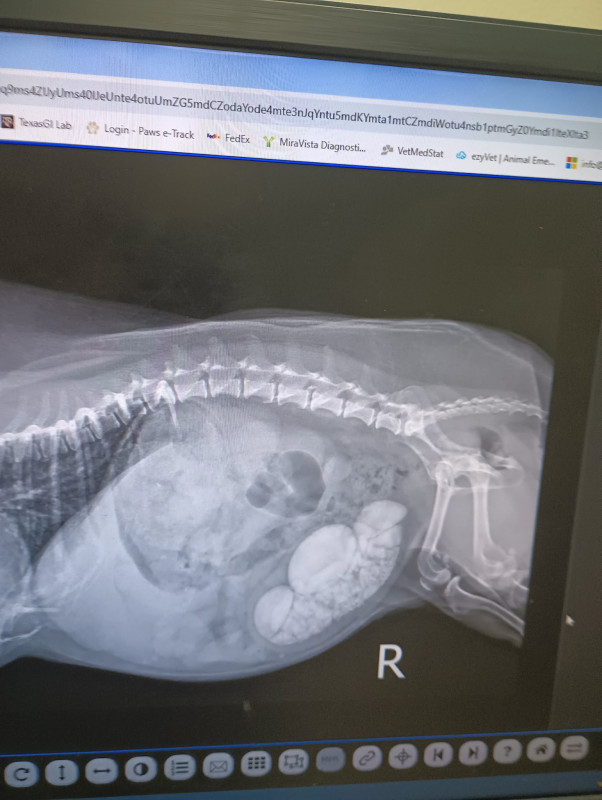

This is Snickers, she is a happy hunky-dory little diva. We adopted her in 2018 and has been a wonderful joy in our life ever since. We are hoping to keep it that way, however we recently found out that she has bladder stones, some as big as a quarter!

She has recently started having lots of accidents due to the lack of space in her little bladder. My husband and I are scared to death that this could kill her. We have acquired estimates on the surgery and are looking at $4,000 to $6,000 that we just don't have. Please help us raise the money to help our poor baby, sh's on limited time.